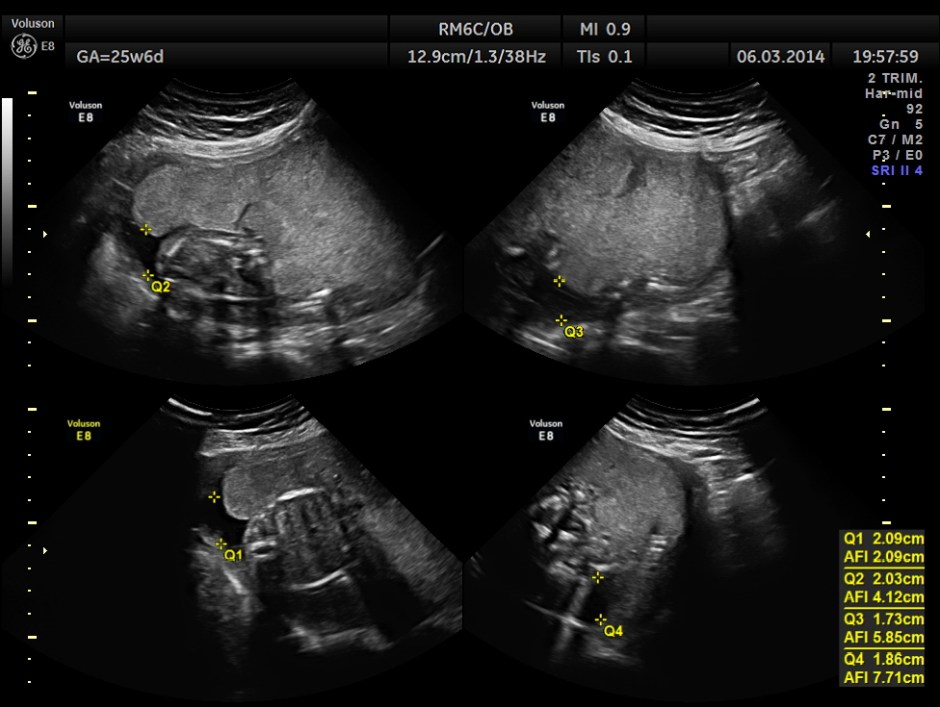

Oligohydramnios seen.